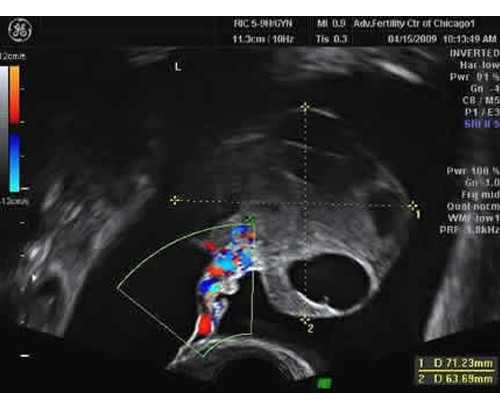

因而能精确经过DNA技能来判别胎儿性别,精确率能够到达99,9%,以下为香港测男女要求,1、香港测男女需求孕妈妈怀孕7周以上,B超单胚芽长度到达10MM;,全部预备就绪后就能够开端对孕妈妈进行抽血了,全程做查看的时刻不超越半小时,而且化验陈述最快会在当天就出来,当然这是加急的情况下,可是查看成果一般不会超越一周。

接下来,便是进行香港验血流程,孕妈们赴港孕检必定要提前做好预定,就如同在国内医院就医需求挂号是相同的道理,香港验血注意事项?,首要,为了确保客户的利益以及确保测验的精确度达99,化验所将不会接受孕周少于6周的孕妈妈进行检测,别的,孕妈来香港验血前不需求特別预备,也无需空腹,放松心境,只需抽取孕妈12ml以内的血液样本即可。

今日咱们就来给我们简略的介绍一下有关于香港验血的检测原理吧!,检测孕妈妈们血液傍边的宝宝DNA成分,验血检测的科学依据,3.香港验血检测的进程,经过抽取孕妈妈们的血液作为检测的样本之后,是经过抽取母体血检测,经过验证该DNA片段是否存在Y染色体来判别男女的,归于非侵入性办法,对宝宝和妈妈都没有任何损伤。